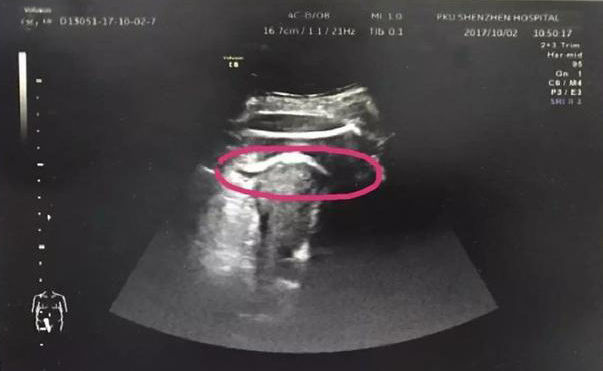

医生初步怀疑患者子宫破裂,当即安排做了B超。检查发现,胎儿的一条腿“踢破”了子宫,进入了腹腔,大腿根正卡在子宫壁上!

▲红色圆圈处是胎儿的腿,已经伸到子宫壁外

医生追问患者病史,原来张女士2016年做过子宫肌瘤剔除术,术后半年就怀孕了。不到2分钟的B超检查,仅凭有限病史,医生快速作出诊断:高度怀疑为疤痕子宫破裂。